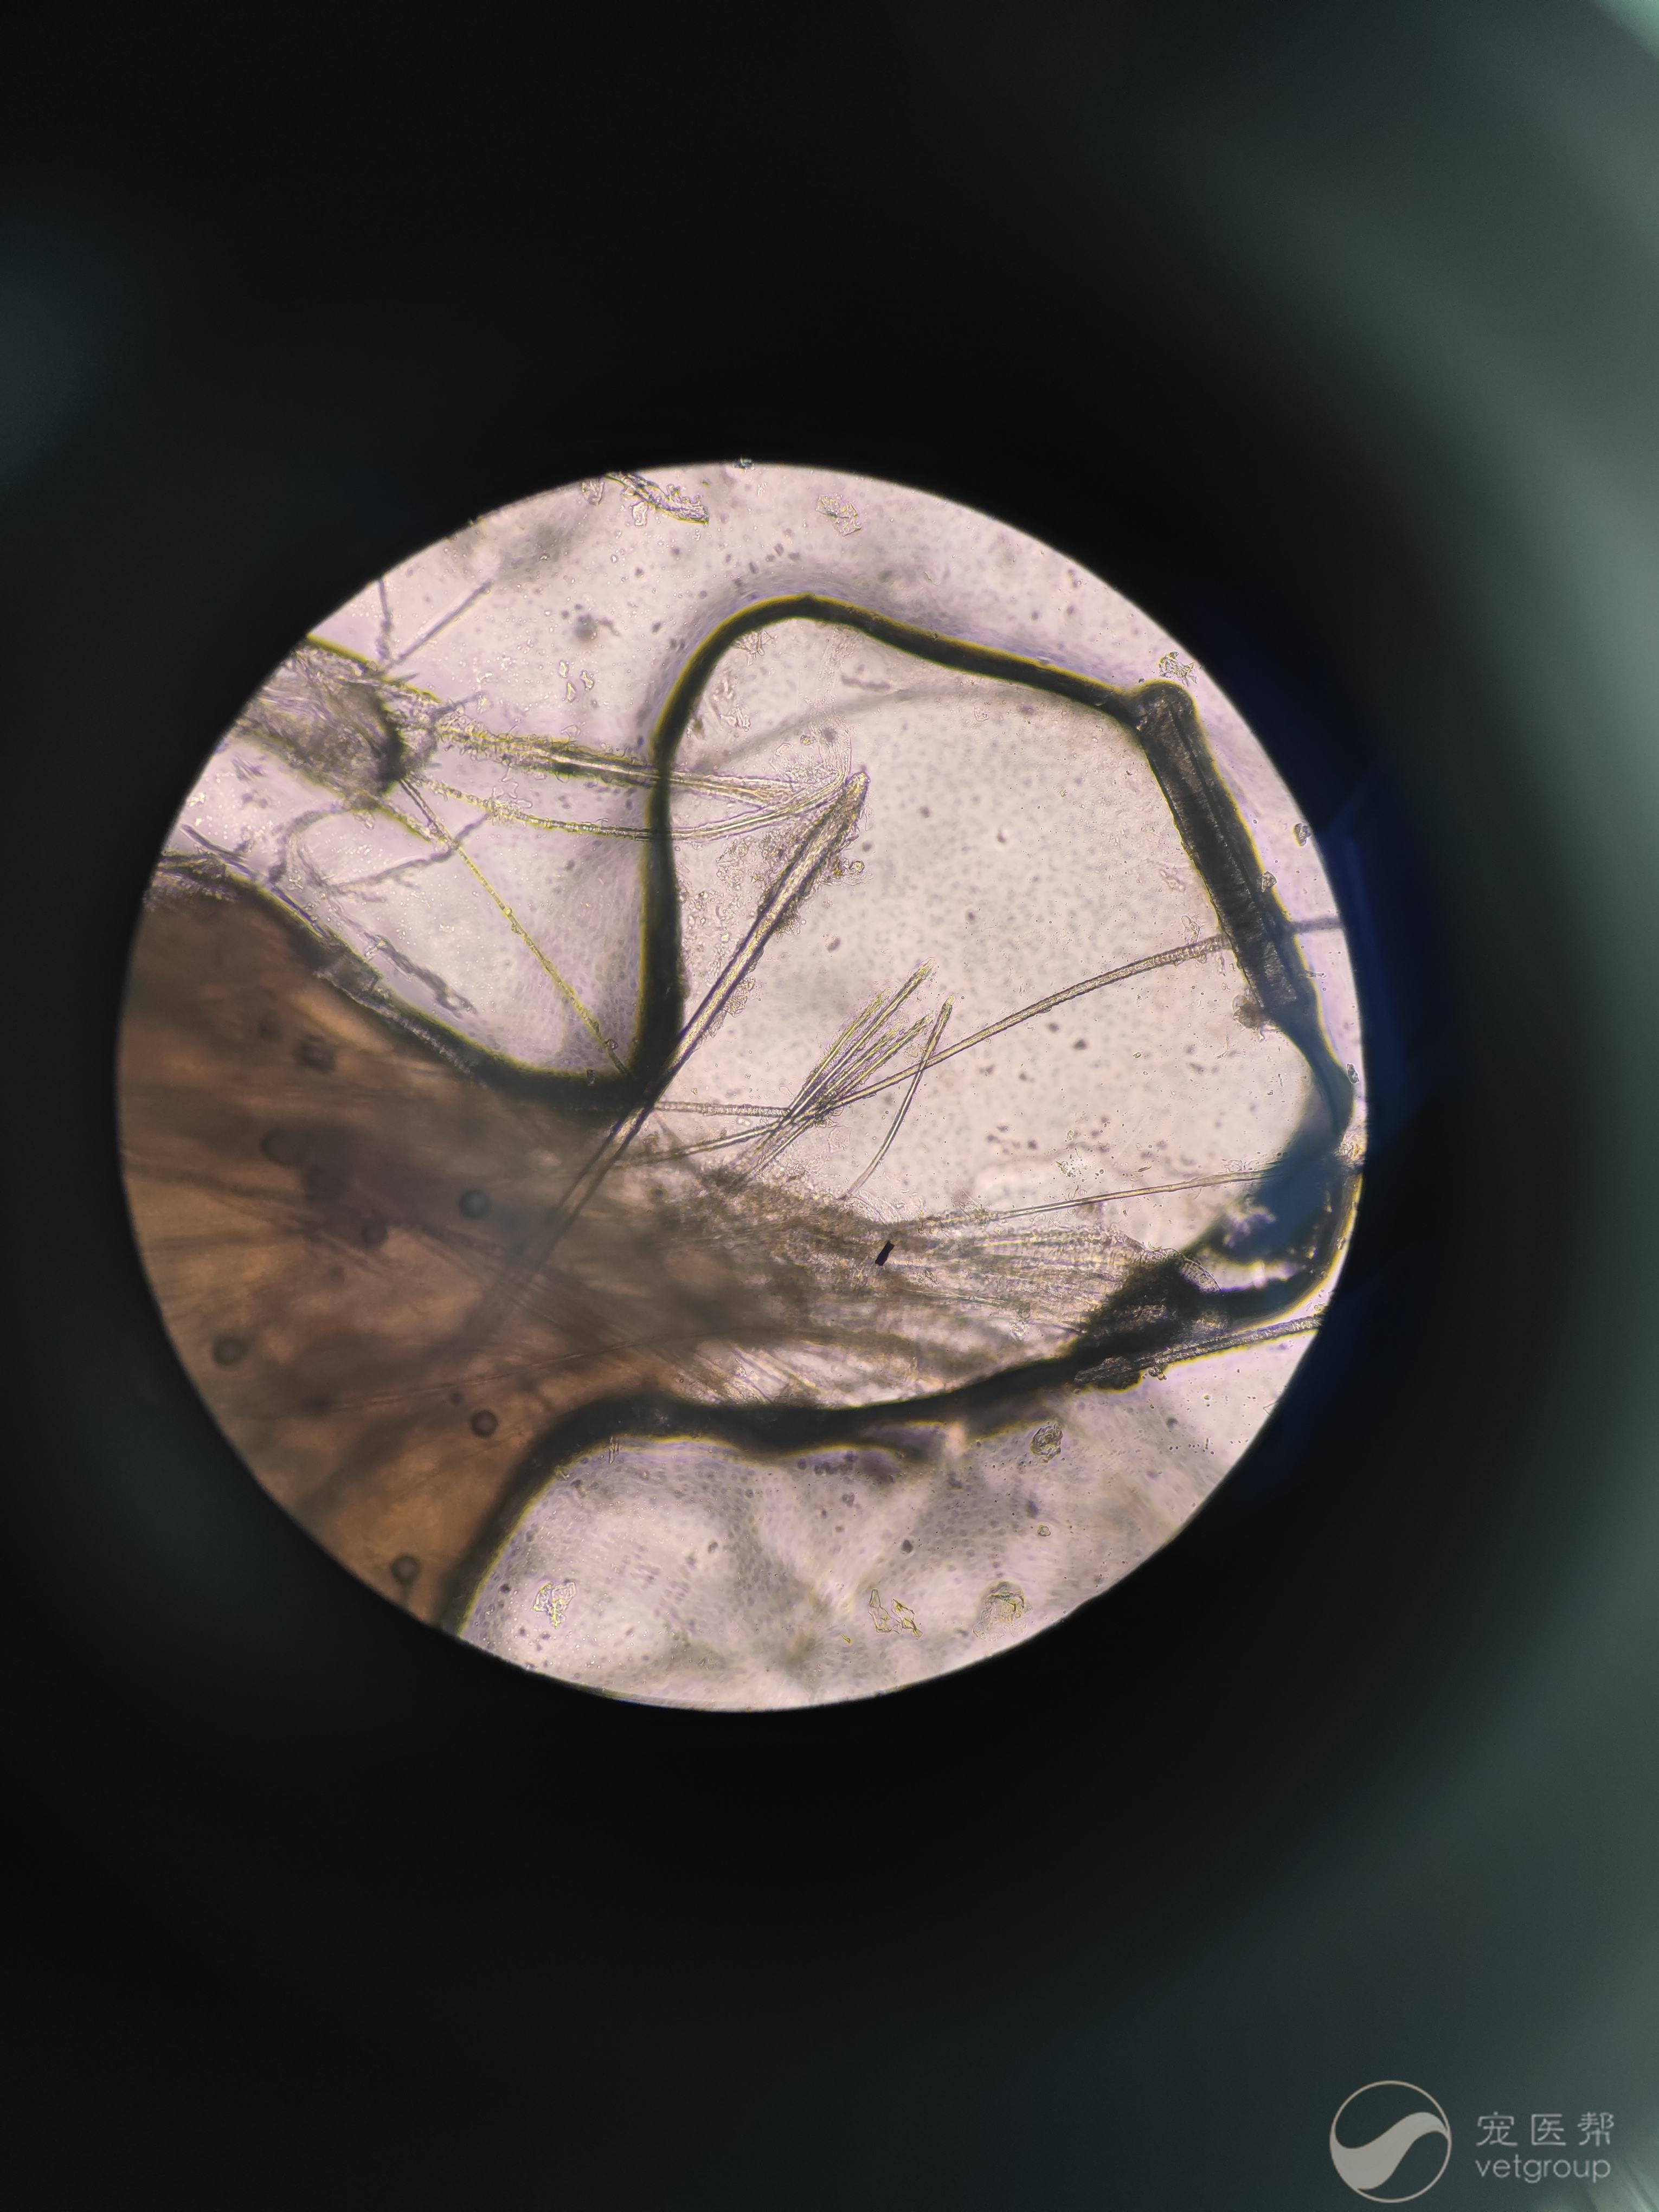

九岁加菲猫全身性病灶,在家用过皮特芬外用药不见好转,带来做镜检见细菌真菌炎性细胞,口服一周汉肤欣,皮下注射头孢噻呋和拜有利,皮肤泡泡爽清洗,没有明显好转,请问各位老师这种情况需要用药浴吗,还需要做什么检查,是否需要换药

而且也没看出有癣菌 能否拍伍德氏灯下的照片?

靶形病变 原因可能是药物刺激 也可能免疫介导皮肤病,需要先停外用药